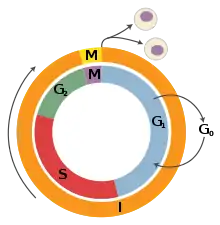

A tumor suppressor gene (TSG), or anti-oncogene, is a gene that regulates a cell during cell division and replication.[1] If the cell grows uncontrollably, it will result in cancer. When a tumor suppressor gene is mutated, it results in a loss or reduction in its function. In combination with other genetic mutations, this could allow the cell to grow abnormally. The loss of function for these genes may be even more significant in the development of human cancers, compared to the activation of oncogenes.[2]

Unlike oncogenes, tumor suppressor genes generally follow the two-hit hypothesis, which states both alleles that code for a particular protein must be affected before an effect is manifested.[7] If only one allele for the gene is damaged, the other can still produce enough of the correct protein to retain the appropriate function. In other words, mutant tumor suppressor alleles are usually recessive, whereas mutant oncogene alleles are typically dominant.

Proposed by A.G. Knudson for cases of retinoblastoma.[7] He observed that 40% of U.S cases were caused by a mutation in the germ-line. However, affected parents could have children without the disease, but the unaffected children became parents of children with retinoblastoma.[8] This indicates that one could inherit a mutated germ-line but not display the disease. Knudson observed that the age of onset of retinoblastoma followed 2nd order kinetics, implying that two independent genetic events were necessary. He recognized that this was consistent with a recessive mutation involving a single gene, but requiring bi-allelic mutation. Hereditary cases involve an inherited mutation and a single mutation in the normal allele.[8] Non-hereditary retinoblastoma involves two mutations, one on each allele.[8] Knudson also noted that hereditary cases often developed bilateral tumors and would develop them earlier in life, compared to non-hereditary cases where individuals were only affected by a single tumor.[8]

- Retinoblastoma protein (pRb). pRb was the first tumor-suppressor protein discovered in human retinoblastoma; however, recent evidence has also implicated pRb as a tumor-survival factor. RB1 gene is a gatekeeper gene that blocks cell proliferation, regulates cell division and cell death.[8] Specifically pRb prevents the cell cycle progression from G1 phase into the S phase by binding to E2F and repressing the necessary gene transcription.[29] This prevents the cell from replicating its DNA if there is damage.